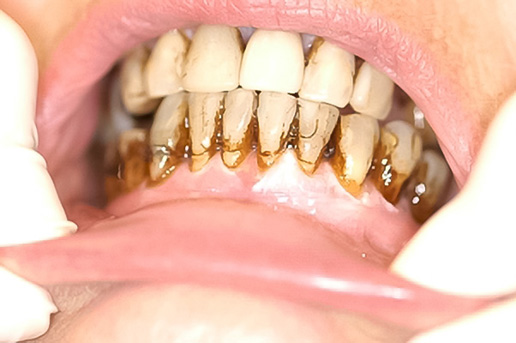

Dominika Oborska-KumaszyńskaCancer Centre London, 49 Parkside, Wimbledon, London SW19 5NB, Wielka Brytania; dominika.oborska-kumaszynska@cancercentrelondon.co.uk (D.O.-K.) Streszczenie Nowotwory głowy i szyi obejmują heterogenną grupę nowotworów wywodzących się z górnych dróg oddechowych i przewodu pokarmowego, zatok przynosowych oraz ślinianek i tarczycy. Optymalne postępowanie w leczeniu tych nowotworów wymaga multidyscyplinarnego podejścia. Radioterapia jest jedną z technik oferowanych w kompleksowym…